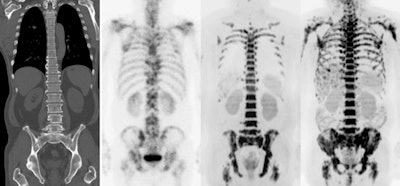

Quantitation of F-18 FDG PET/CT studies is mainly performed by standardized uptake values (SUVs), although other metrics such as metabolic active tumor volume and total lesion glycolysis are being introduced in research and the clinic.

"The most frequently used metric to assess the intensity of FDG accumulation in cancer lesions is, however, still the maximum SUV," they continued. "SUV represents the tumor tracer uptake normalized for injected activity per kilogram body weight. SUV and any of the other PET quantitative metrics are affected by technical (calibration of systems, synchronization of clocks, and accurate assessment of injected F-18 FDG activity), physical (procedure, methods, and settings used for image acquisition, image reconstruction, and quantitative image analysis) and physiological factors (FDG kinetics and patient biology/physiology)."

To mitigate these factors, guidelines have standardized imaging procedures and harmonized PET/CT system performance at a European level. Newer targeted PET agents are only assessed qualitatively on their distribution.